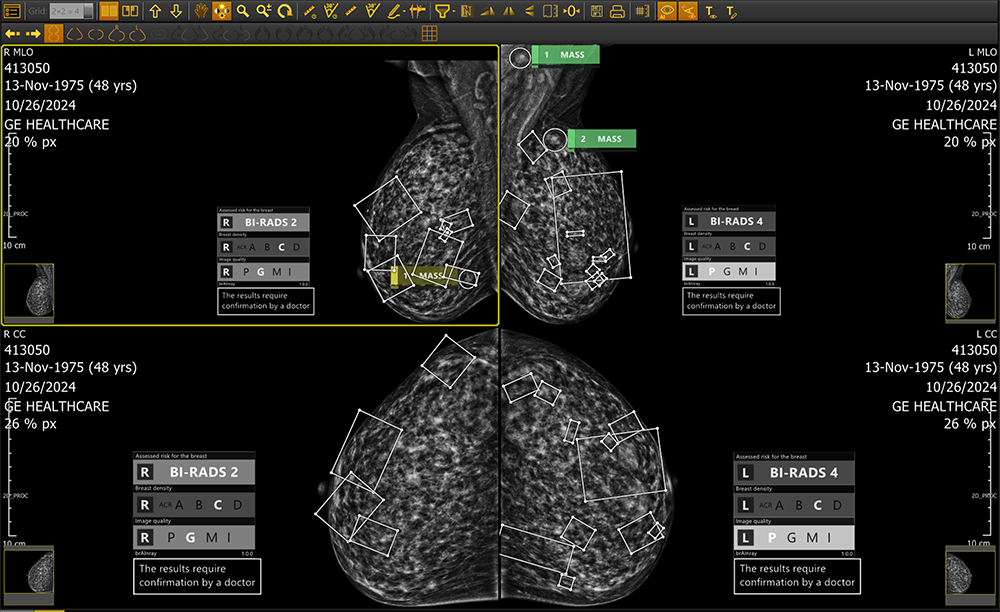

Whether deployed on-site or via the cloud, brAInray® seamlessly integrating with any PACS system, brAInray® analyzes full-field digital mammograms (FFDM) to detect and mark suspicious regions—highlighting calcifications, masses, asymmetries, and architectural distortions. It categorizes findings using ACR BI-RADS® standards and delivers automatic structured DICOM reports for clear, consistent clinical insights.